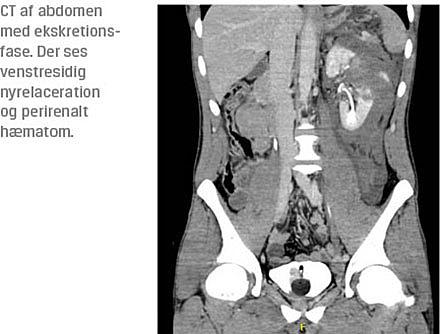

Der bør foretages abdominal CT med kontrast og ekskretionsfase i tilfælde af: 1) penetrerende traume eller 2) stumpt traume med: a) makroskopisk hæmaturi,

b) kredsløbsinstabilitet eller c) udfyldning/kontusion i flanken. Graden af hæmaturi korrelerer ikke med nyreskadens sværhedsgrad, men hæmodynamisk stabile patienter med mikroskopisk hæmaturi har en lav risiko for signifikant nyreskade [4]. Omvendt kan der forekomme tilfælde med nyretraumer uden hæmaturi. Dette kan skyldes pedikelavulsion, trombose af segmentarterier eller afrivning af ureter. Imidlertid vil disse tilfælde uden undtagelse skyldes situationer, hvor traumemekanismen er stumpt traume med voldsom deceleration eller et penetrerende traume, og alene på baggrund af dette vil der i praksis blive udført en standardiseret traumeskanning. Nyretraumer diagnosticeres ofte i forbindelse med den sekundære gennemgang ved traume-CT. I dette tilfælde skal skanningen, såfremt patientens kliniske tilstand tillader det, suppleres med en ekskretionsfase, således at de fraførende urinveje visualiseres.